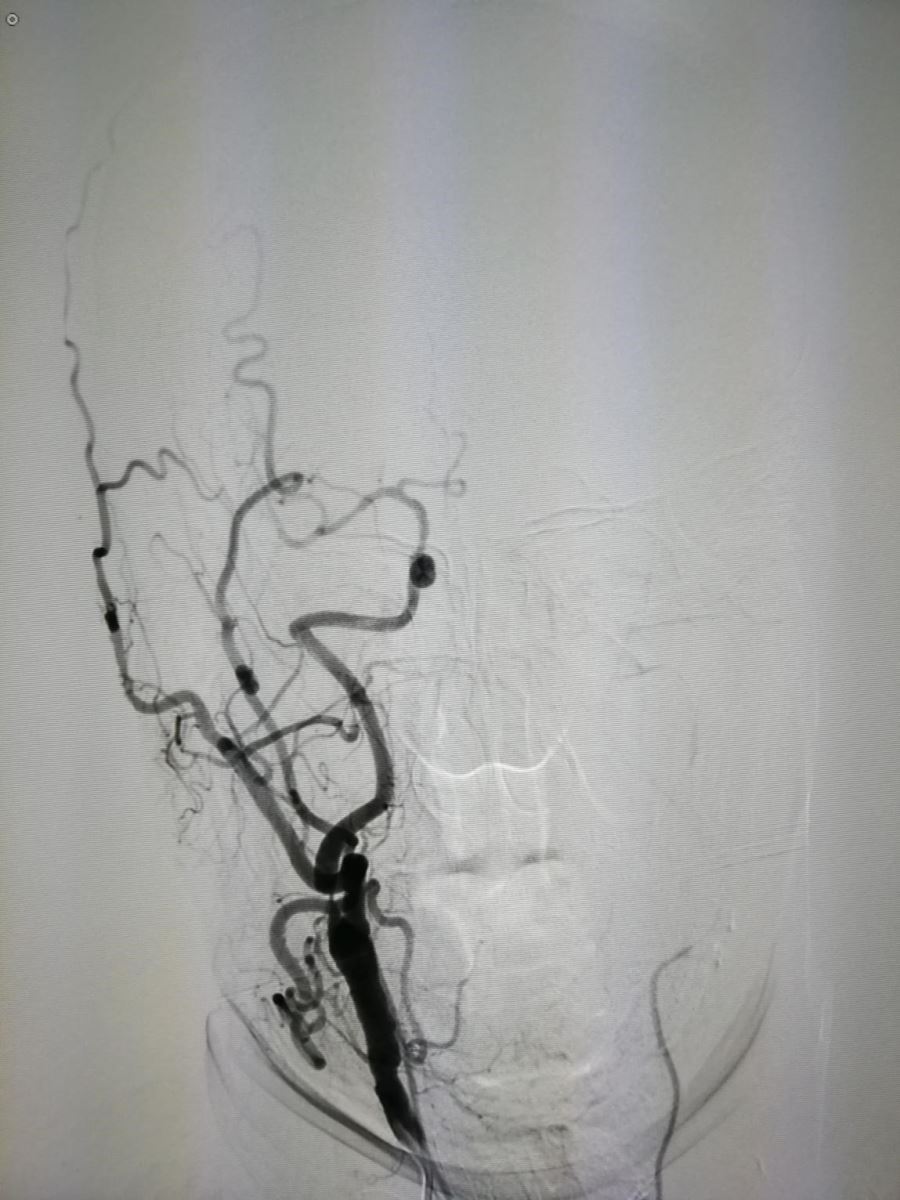

如果单看颅内血管成像,无需介入治疗,但如果连同颈部动脉血管成像(图2、3)。

.jpg)

图2 图3

则患者有必要行血管内支架植入治疗(2018-09-12为该患行支架植入治疗)。图4为术后正位,图5为正位支架位置。